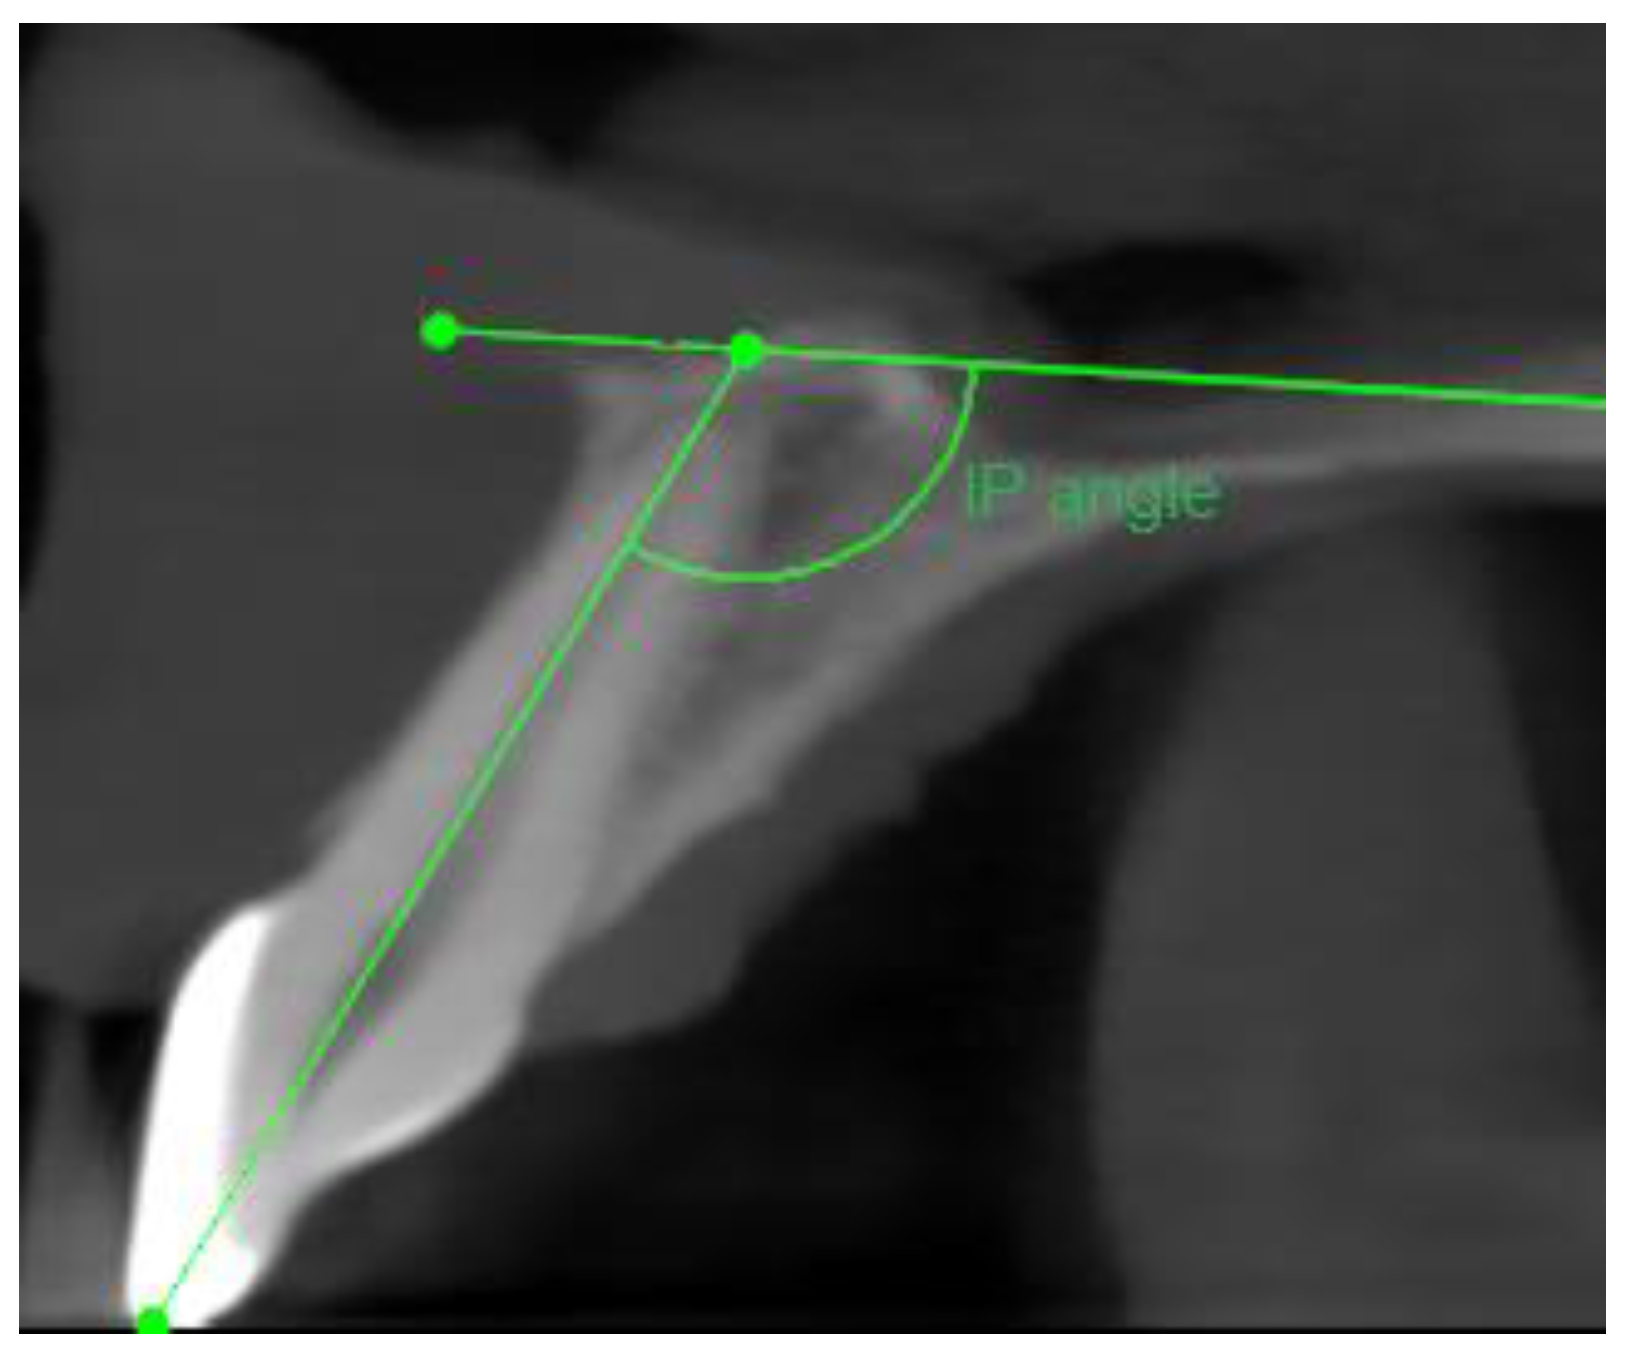

- Sagittal plane:

- Angle formed by the long axis of the incisor and the palatine plane—CP angle.

- Angle formed by the long axis of the incisive canal and the palatine plane—IP angle.